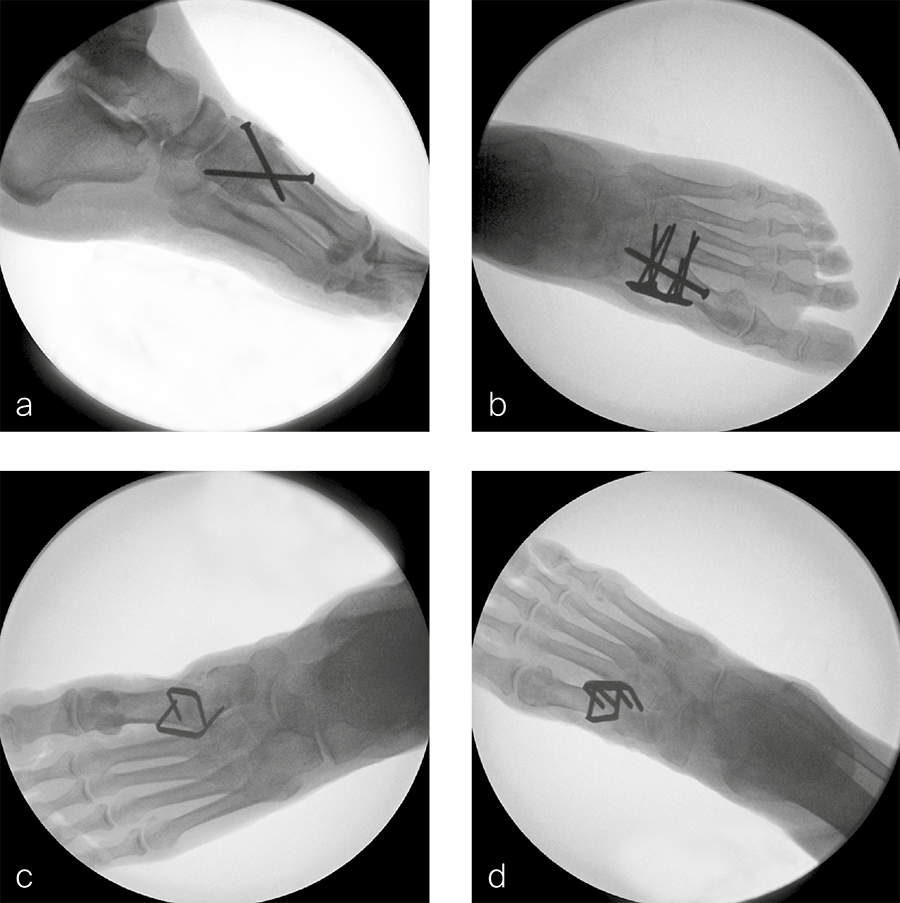

- Crossed-screw fusion with two DPS 4.0 mm fully threaded stainless steel lag screws inserted in standard fashion, ie, first screw from the first metatarsal to medial cuneiform and second screw from medial cuneiform to the plantar base of the first metatarsal (Fig 2a).

- Plate-and-screw fusion with a DPS 4.0 mm standard midfoot fully threaded stainless steel cortex screw, inserted cortically in lag fashion, and a DPS 6-hole TMT-1 stainless steel VA Fusion Plate 2.4/2.7 (Fig 2b).

- CCI fusion with 2 two-leg staples DPS SE-1818TI BME SPEEDTITAN™ and DPS SE-2520TI BME SPEEDTITAN™ placed orthogonally to each other (Fig 2c).

- CCI fusion with 1 two-leg staple DPS EL-1818S2 BME ELITE® and 1 four-leg staple DPS EL-2520S4 BME ELITE®, placed orthogonally to each other (Fig 2d). All fusion procedures were performed on intact feet with preparation of the joint articulations and under image intensification control according to the implant manufacturer's guidelines.